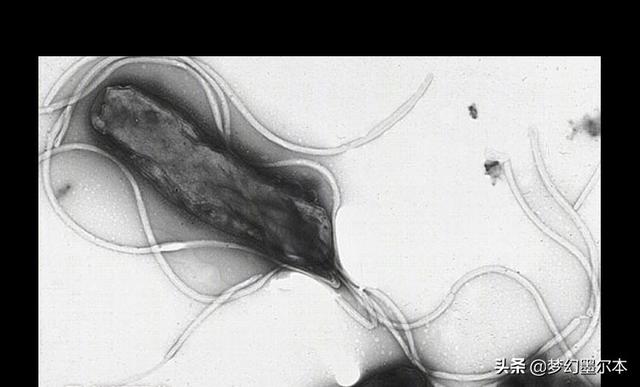

第一に、感染症について触れなければならない。そして最も注目すべきは、世界保健機関(WHO)が明らかにしていることだ。ヘリコバクター・ピロリ感染は胃癌の発生と強く関連しているピロリ菌に感染した初期のように、急性の炎症が起こり、その後、どんどん長い期間をかけて胃に慢性的な炎症性変化を引き起こし、前がん病変につながる可能性がある。そのため、1994年に世界保健機関(WHO)の国際がん研究機関(IARC)によって、ピロリ菌感染は発がん性物質群として定義された。もちろん、ピロリ菌以外にもEBVなどの感染因子がある。

まず感染因子だが、ピロリ菌の相互感染が考えられる!ヘリコバクター・ピロリの感染は人から人へであり、人が唯一の感染源である。この種の感染は、口から口へ、口から口へ、糞便から口へであり、非常に広がりやすい。たとえ一緒に食事をしたとしても、共用の箸を使わなければ、夫婦のどちらかがヘリコバクター・ピロリに感染していることになり、もう一方も非常に感染しやすい。そして、最終的に除菌に成功したとしても、再感染しやすい。

もちろん、ヘリコバクター・ピロリ菌に感染したからといって、必ず胃がんになるわけではなく、そのほとんどに罹患はないが、長期にわたるヘリコバクター・ピロリ菌の感染は、慢性胃炎、消化性潰瘍、胃がんなどの一連の臨床疾患を引き起こす可能性が高く、リンパ腫などもこのヘリコバクター・ピロリ菌の感染と明らかに関連しており、ヘリコバクター・ピロリ菌の感染も発がん物質の一種として論文で言及されている;

つまり、夫婦ともに胃がんなのだ。最大の可能性は、彼らがすべてヘリコバクター・ピロリ菌に感染していることであり、通常、不健康な生活や食習慣は、胃の病気の数の出現によって引き起こされ、殺菌する必要性のために、見て、治療するためにタイムリーではないかもしれませんが、また、タイムリーな方法で四重療法を取らなかった、その結果、ヘリコバクター・ピロリ菌の長期感染に起因する。

お招きありがとうございます!胃がんの原因には、胃ポリープ、萎縮性胃炎、ピロリ菌感染、長期高塩分食、長期漬物食、遺伝などいろいろあります。しかし、夫婦同時に胃がんが発覚する最も可能性の高い理由は、胃がんになりやすいピロリ菌に二人とも感染していること(同じ茶碗、箸、キスなど)である。ピロリ菌は強力な胃酸の中で生存・繁殖できる唯一の細菌で、発がん性細菌の一種として、中国人の感染率は約60%、慢性胃炎の多くはピロリ菌の感染が関係している。中国医科大学によると、ピロリ菌に感染している人の少なくとも1%が癌化するという。現在、検査は特に簡単で、病院で息を吹きかければ(違和感なく)陰性か陽性かがわかる。治療は複雑ではない。西洋医学では、オメプラゾール(またはランソプラゾール)+コロイド状ビスマスペクチン+アモキシシリンカプセル+メトロニダゾール、プロバイオティクス、漢方薬では梅干(おやつとして食べられる)。14日間服用し、夫婦で同時に治療する。効果は非常に良い。

以下はヘリコバクター・ピロリの図である。

原因3:ヘリコバクター・ピロリ感染

胃がんの発生にはヘリコバクター・ピロリ菌の感染が関係していることがわかっており、夫婦のどちらかがヘリコバクター・ピロリ菌に感染すると、治療が間に合わなければ胃炎や胃潰瘍などの病変が発生しやすく、長い年月をかけてがん化する。一方、ヘリコバクター・ピロリ菌は唾液などの口腔分泌物からも感染するため、夫婦ともに食生活の衛生に気を配らなければ、同時にヘリコバクター・ピロリ菌に感染しやすい。